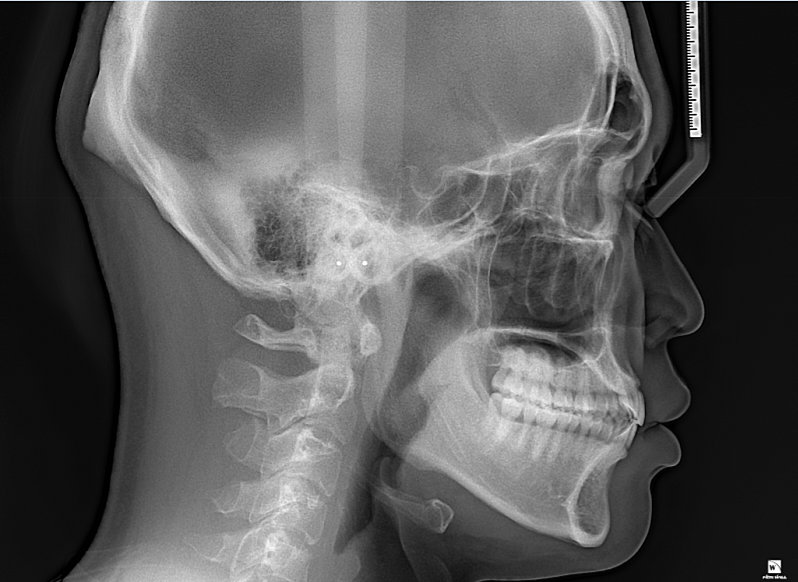

• 1번 째 사진